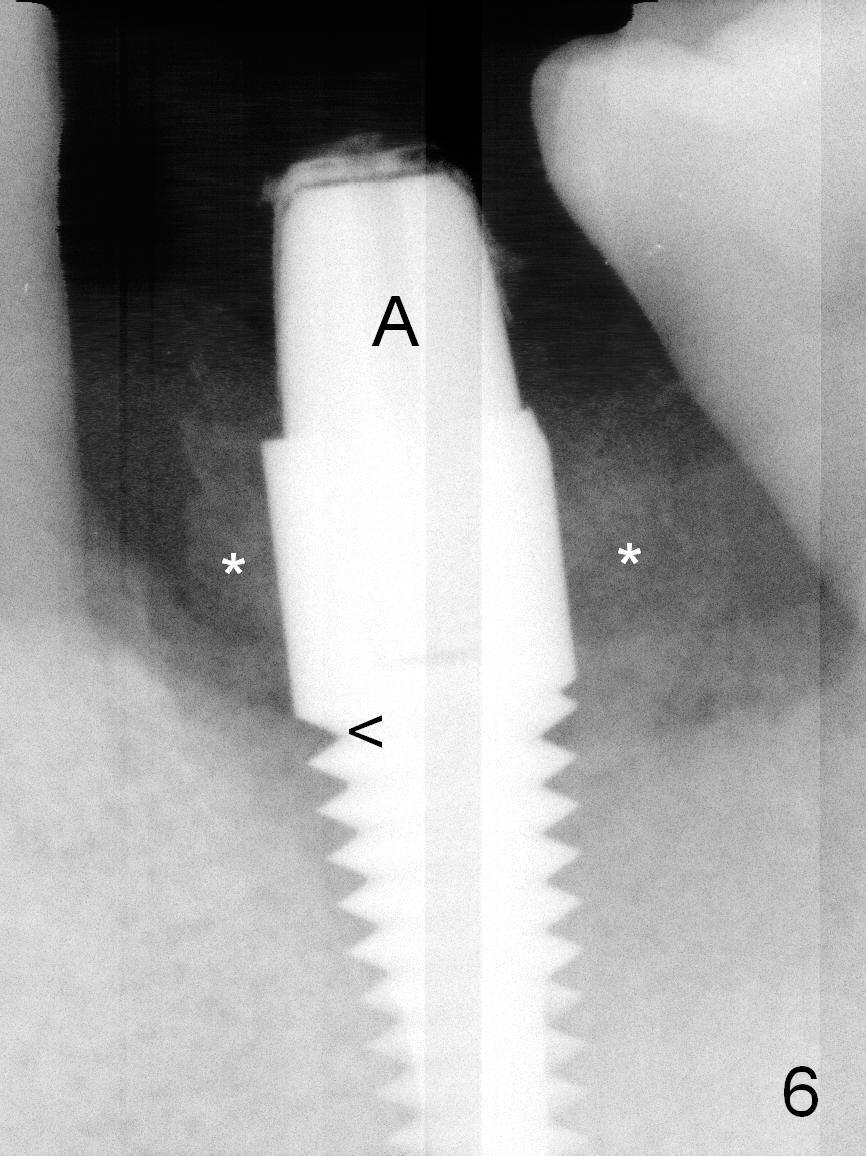

The implant is placed lower by 1 thread (compare arrowheads in Fig.5,6). Bone graft (Fig.6 *) and Osteoplug are placed in the remaining socket (mainly mesiobuccodistally). An abutment (A) is placed for immediate provisional.